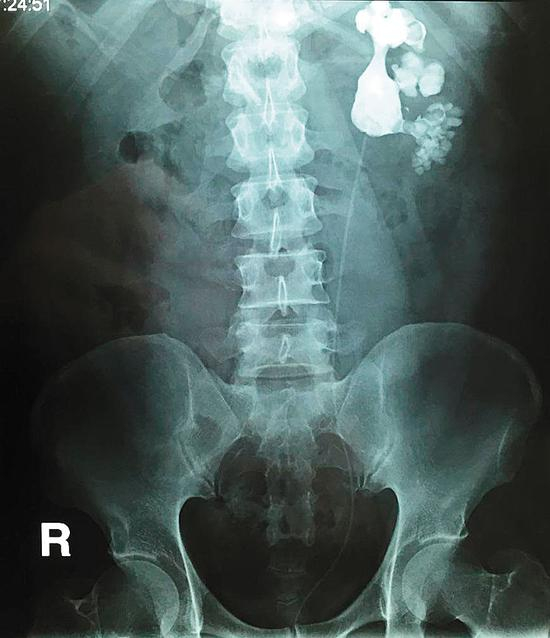

陈先生的儿子陈帅(化名)住在城里,知道父亲有这个毛病,前段时间,他带父亲去新桥医院做B超检查,片子上显示他右肾内长满了结石,形状像鹿角一样。当时,陈先生不敢相信,对检查结果持有怀疑态度。最终,陈先生在儿子的劝导下做了手术,医生通过腹腔镜在陈先生的肾盂上开刀,取出了143块结石。